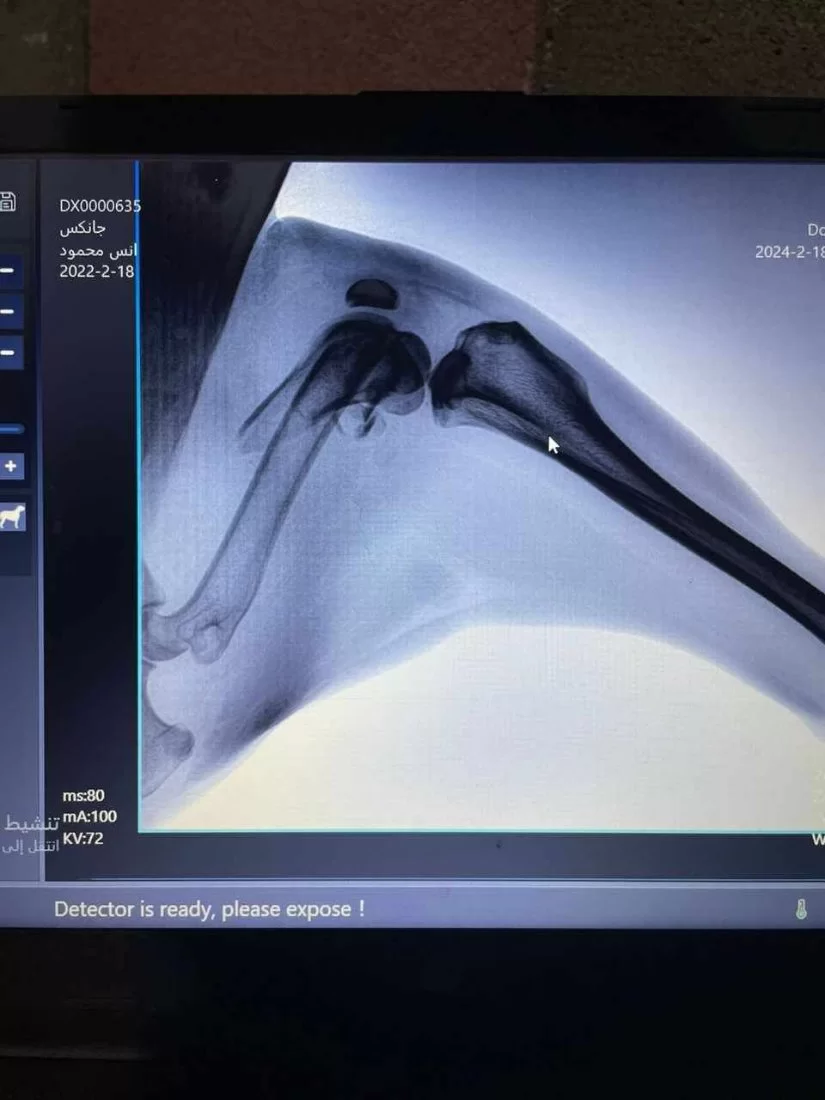

عملية تثبيت كسر مركب في كلب مالينو ( الراعي البلجيكي)

تم اليوم الموافق 21 فبراير 2024 إجراء عملية جراحية لكلب يعاني من كسر مركب في منطقة الركبة حيث قام اساتذة القسم بالتعاون مع طلبة السنه الخامسة من تثبيت الكسر بواسطه أسياخ بلاتينية وايضا تم استخراج اجسام غريبة كانت قد اخترقت الجلد اثناء تعرض الحيوان للحادث.